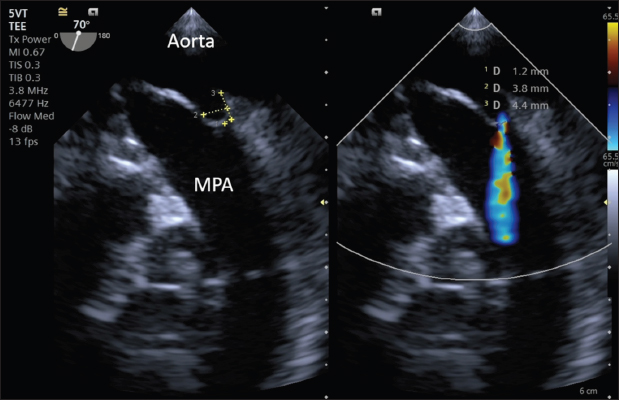

A transthoracic echocardiogram (TTE) (Siemens Acuson Juniper, Probe: 8V4, Siemens Healthcare, Erlangen, Germany) revealed mild left atrial and left ventricular dilation: Left atrium/aorta ratio: 1.8 ( reference value < 1.6), normalized to body weight), left ventricular internal diastolic diameter: 1.98 (reference value: ≤ 1.7), and left ventricle apical four-chamber view end-diastolic volume (Simpson biplane method): 23.6 mL (reference value < 20.1 mL), (Wess et al. 2021). It also revealed a small PDA, with approximate MDD and ampulla diameters of 1.2 mm and 3.7 × 7 mm, respectively, and a length of 7 mm (Fig. 2).

Fig. 2. Transthoracic echocardiography, cranial left lateral view, optimized for PDA visualization and its measurement (A) and and left-to-right flow on CFM Doppler (Dual-mode).